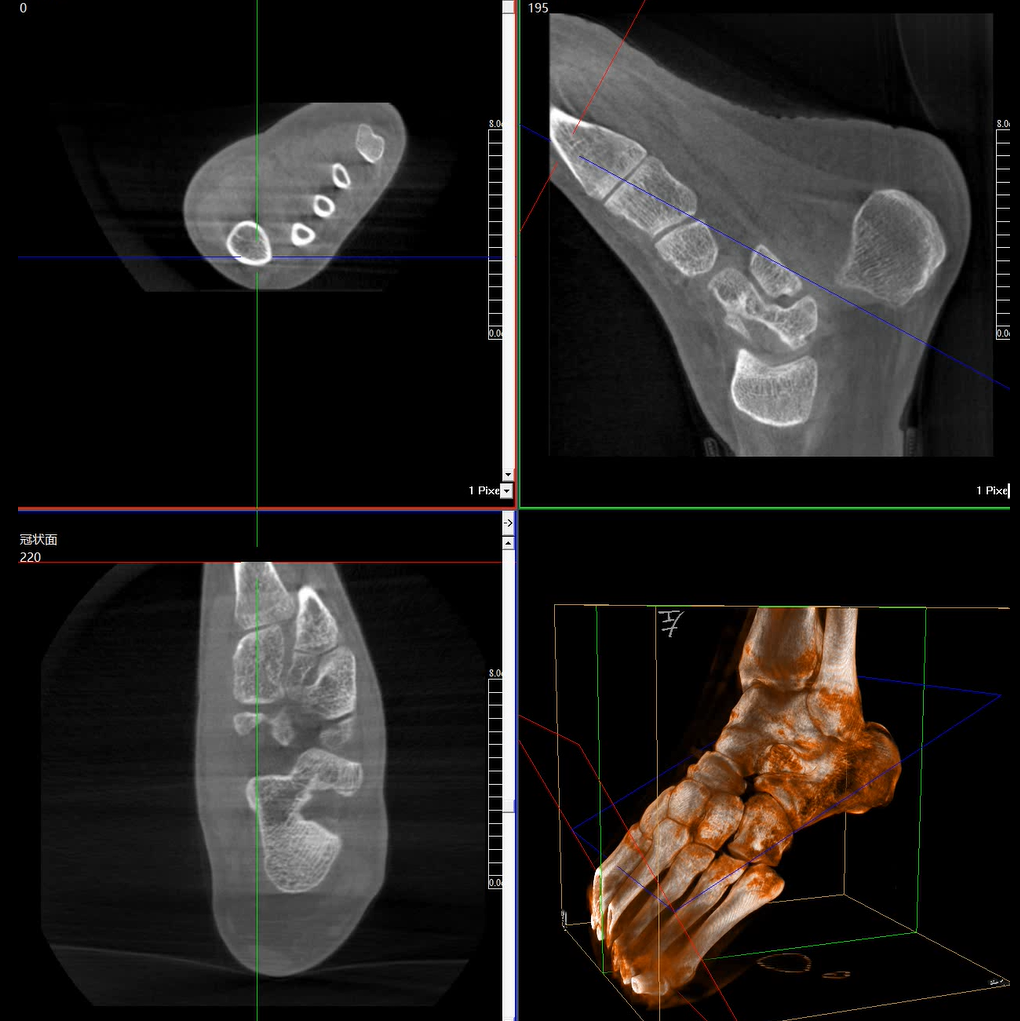

術(shù)中三維成像和橫斷面圖像提供多角度的手術(shù)診斷信息,輔助醫(yī)生進(jìn)行術(shù)中評(píng)估判斷,諸如骨折復(fù)位情況和內(nèi)植入螺釘?shù)某叽绾臀恢茫o助手術(shù)更好地完成。

提供更大的術(shù)中三維成像視野,采集更多圖像信息,可一次拍全全段頸椎、全段腰椎、七節(jié)胸椎、雙側(cè)骶髂關(guān)節(jié)、股骨頭及單側(cè)盆骨。